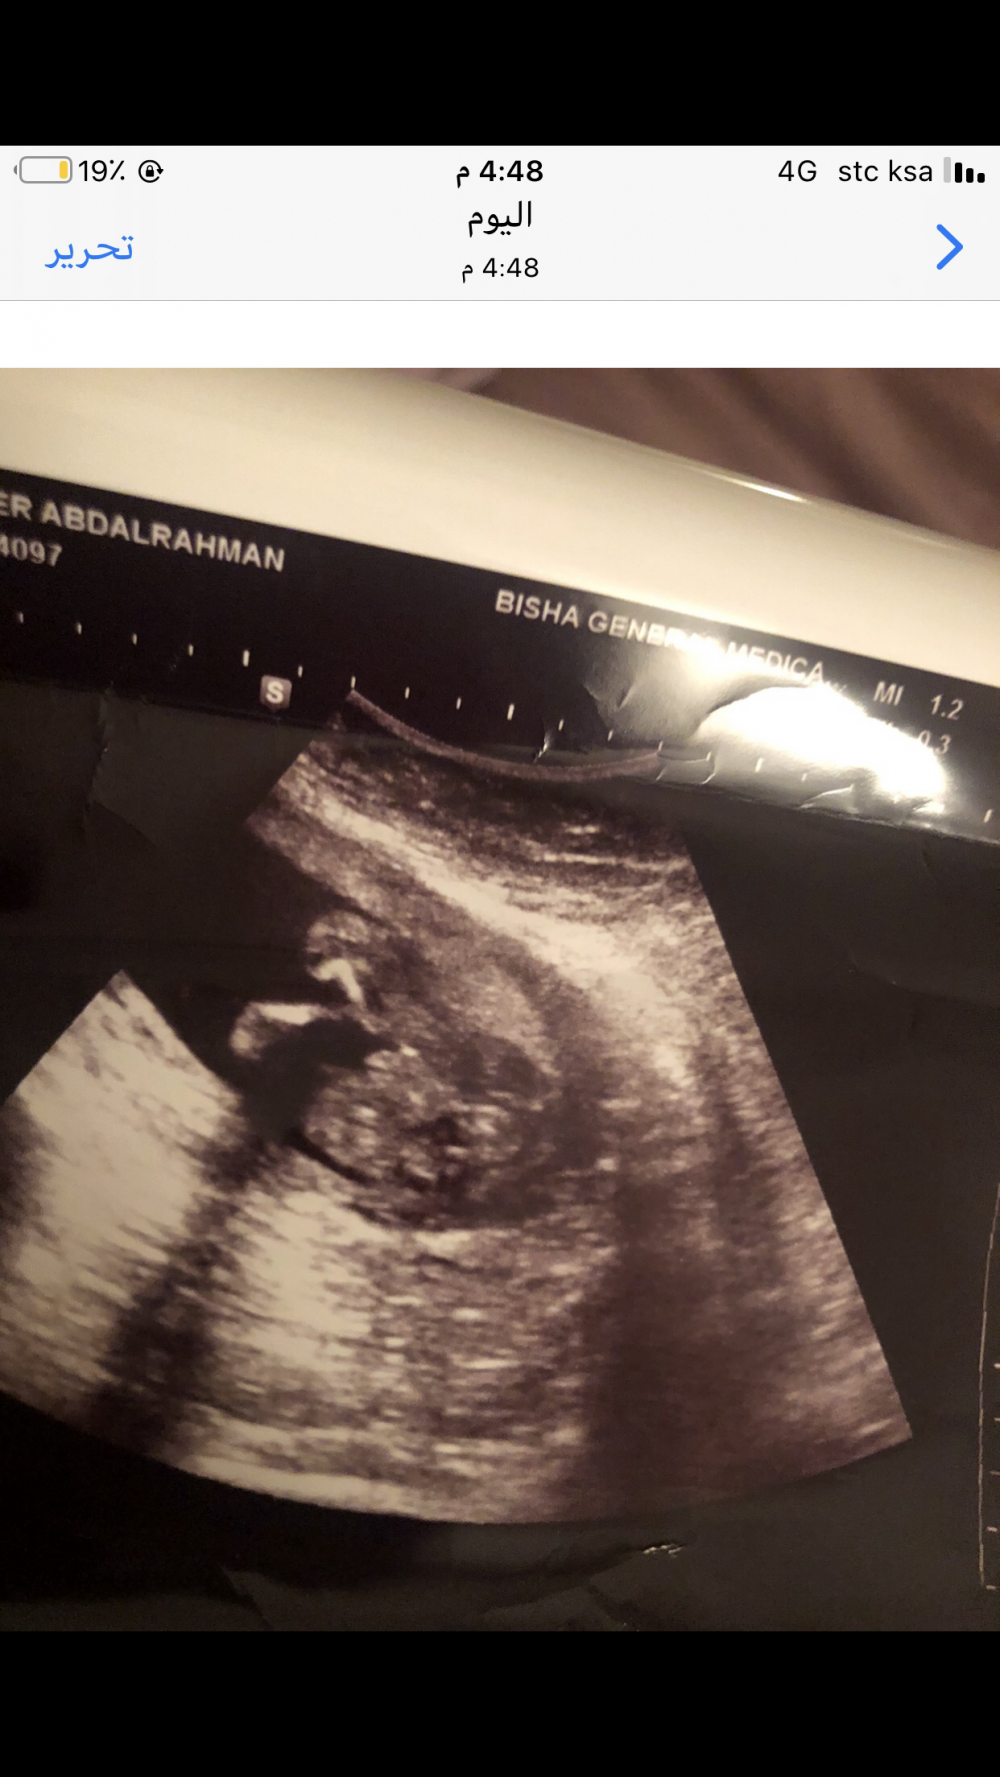

هذا سوناري بين الارجل هي قالت لي ولد بس بتأكد منكم 😂

طيب بنات بما ان بعضكم خبرة بالسونار هذا سوناري بين الارجل هي قالت لي ولد بس بتأكد منكم 😂

ولد 💙

واضح العضو فيه